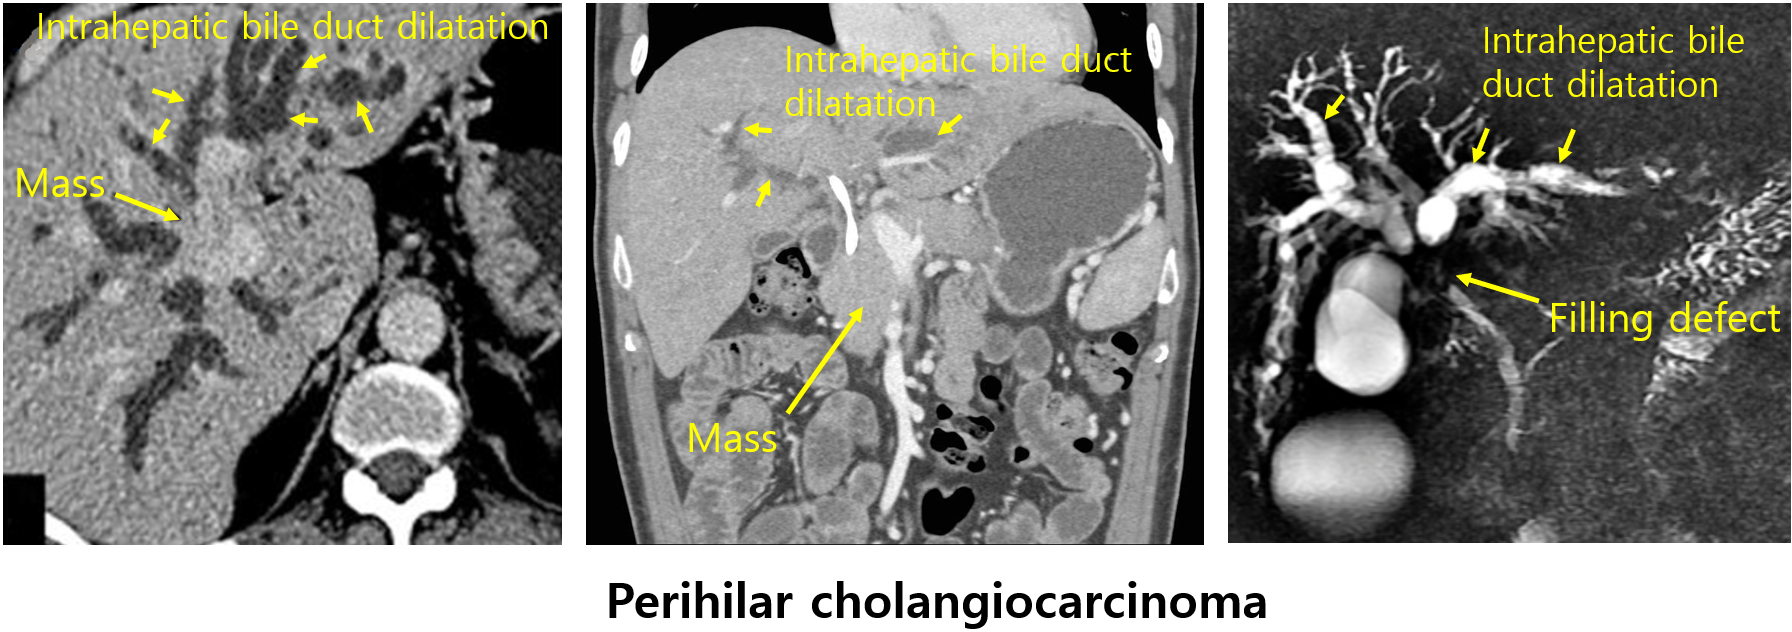

1) 복부 CT/MRI: 종양의 유무, 위치, 침윤 정도, 전이 평가에 적합

(2) 간문부담관암: 간문부 주변의 종양 + intrahepatic bile duct의 확장

(3) 원위부담관암: Distal CBD의 종양 + CBD/CHD/intrahepatic duct의 확장

2) 담관조영술: MRCP, ERCP, PTC 등

• 종양의 담도 내 침범 범위를 파악하는데 적합

• CT, MRCP 등: 담관 mass + proximal bile duct dilatation